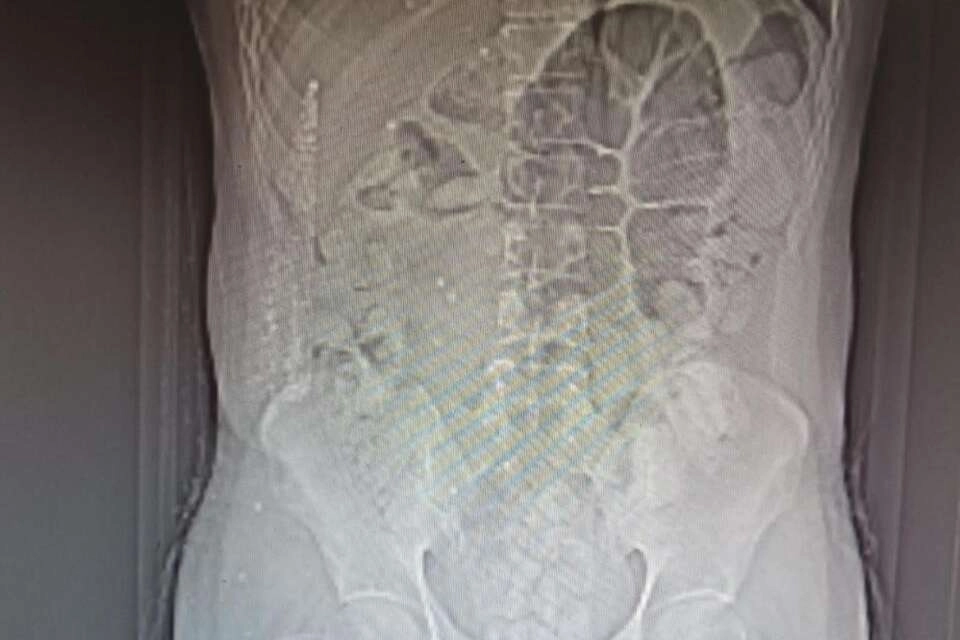

İl Emniyet Müdürlüğü Narkotik Suçlarla Mücadele Şube Müdürlüğü ile Kaçakçılık ve Organize Suçlarla Mücadele Şube Müdürlüğü ekiplerince yapılan ortak çalışmada; uygulama noktasında durdurulan, İran otobüsünde yolcu olarak bulunan İran uyruklu şüpheli M.K. (31) isimli kişiye yapılan tomografi çekiminde mide ve bağırsak kısmında uyuşturucu olabileceğini değerlendirilen çok sayıda yabancı cismin olduğu tespit edildi. Yapılan tetkikler neticesinde M.K.’nın midesinden 64 parça halinde 711,86 gr gelen Afyon Sakızı ele geçirildi. Şüpheli M.K. emniyetteki işlemlerinin ardından sevk edildiği adliyede tutuklanarak cezaevine gönderildi.